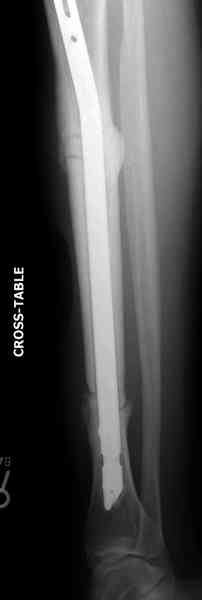

Недавно на нашей ежемесячной Morbidity&Mortality

conference мы разбирали похожий случай, ложный сустав большеберцовой кости после резекции опухоли.

К нашему онкологу-ортопеду обратился больной с жалобами на боли в голени, из рассказа - год назад была сделана биопсия большеберцовой кости, но название заболевания "не запомнил”.

Оперирован в военном госпитале с заменой сегмента

аллокостью большеберцовой кости и после демобилизации явился для постоянного наблюдения по месту жительства.

Наши имели проблему со сращением, пришлось им сделать динамизацию, дополнительную аутопластику.

Снимки представлены.